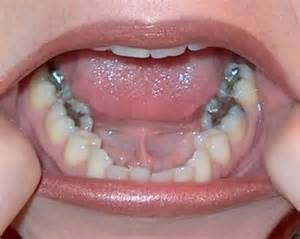

A tooth filling is where material (such as porcelain inlay/onlay or composite) is inserted into a damaged or decayed tooth to restore its original shape and function. This can be either a dental inlay (fills centre of tooth) or onlay (more extensive than an inlay and can cover up to the entire biting surface of a tooth).

Fillings are most commonly used to prevent further damage to a tooth when decay is present. By removing the bacteria and closing the affected area off, no further tooth decay can occur.

Porcelain fillings – inlay/onlay are tooth coloured and are created to match the current aesthetics of teeth. A porcelain filling is virtually indistinguishable from other healthy teeth and can last up to 20 years.

Composite fillings are similar to porcelain fillings; however, they can last 5-10 years when applied to teeth.

Gold fillings need to be created in a lab to fit the tooth cavity and are then cemented into place. They are the most expensive type of filling and require multiple visits. Gold fillings are well received by the surrounding gum tissue and can last for more than 20 years.

Amalgam fillings were the most common, cheapest filling available. However, amalgam fillings contain mercury and are not commonly used in Australia. Moreover, this type of filling can expand and contract in heat which can cause teeth to crack. For this reason, we do not offer amalgam fillings at Coastal Dental Care. Instead, we offer to replace old amalgam fillings with healthier tooth coloured fillings.